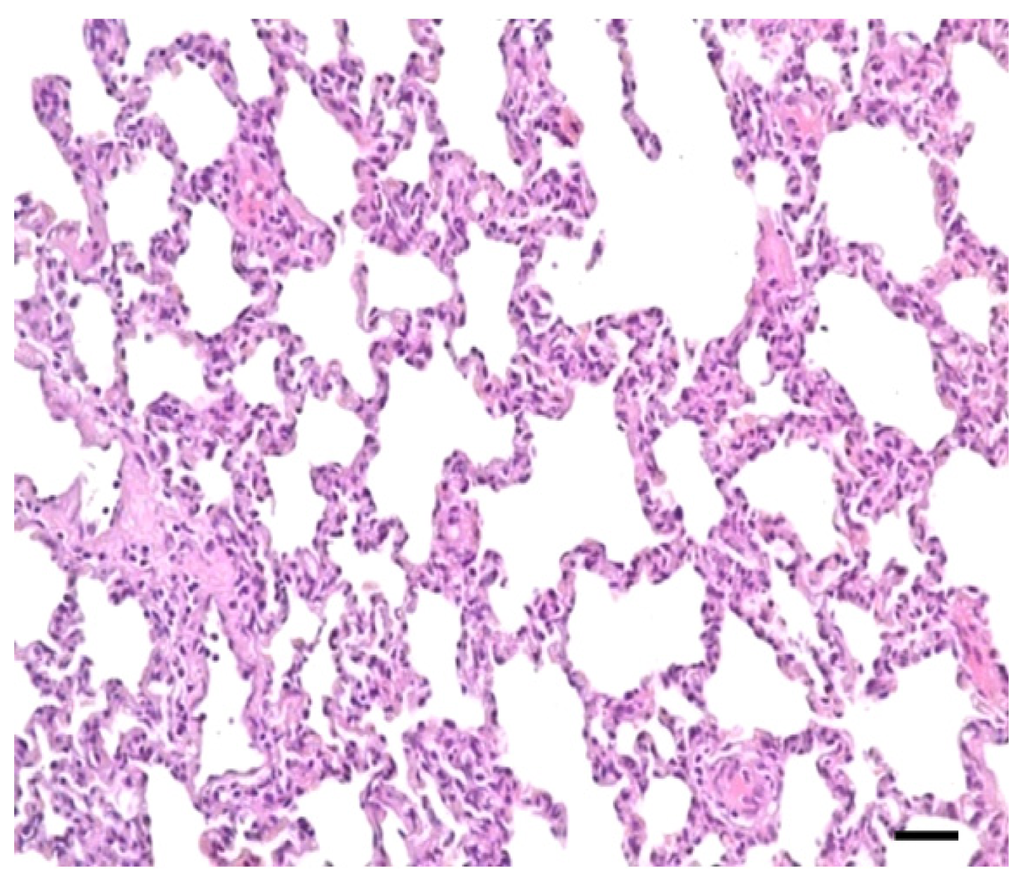

2.1. Clinical Symptoms and Necropsy Findings